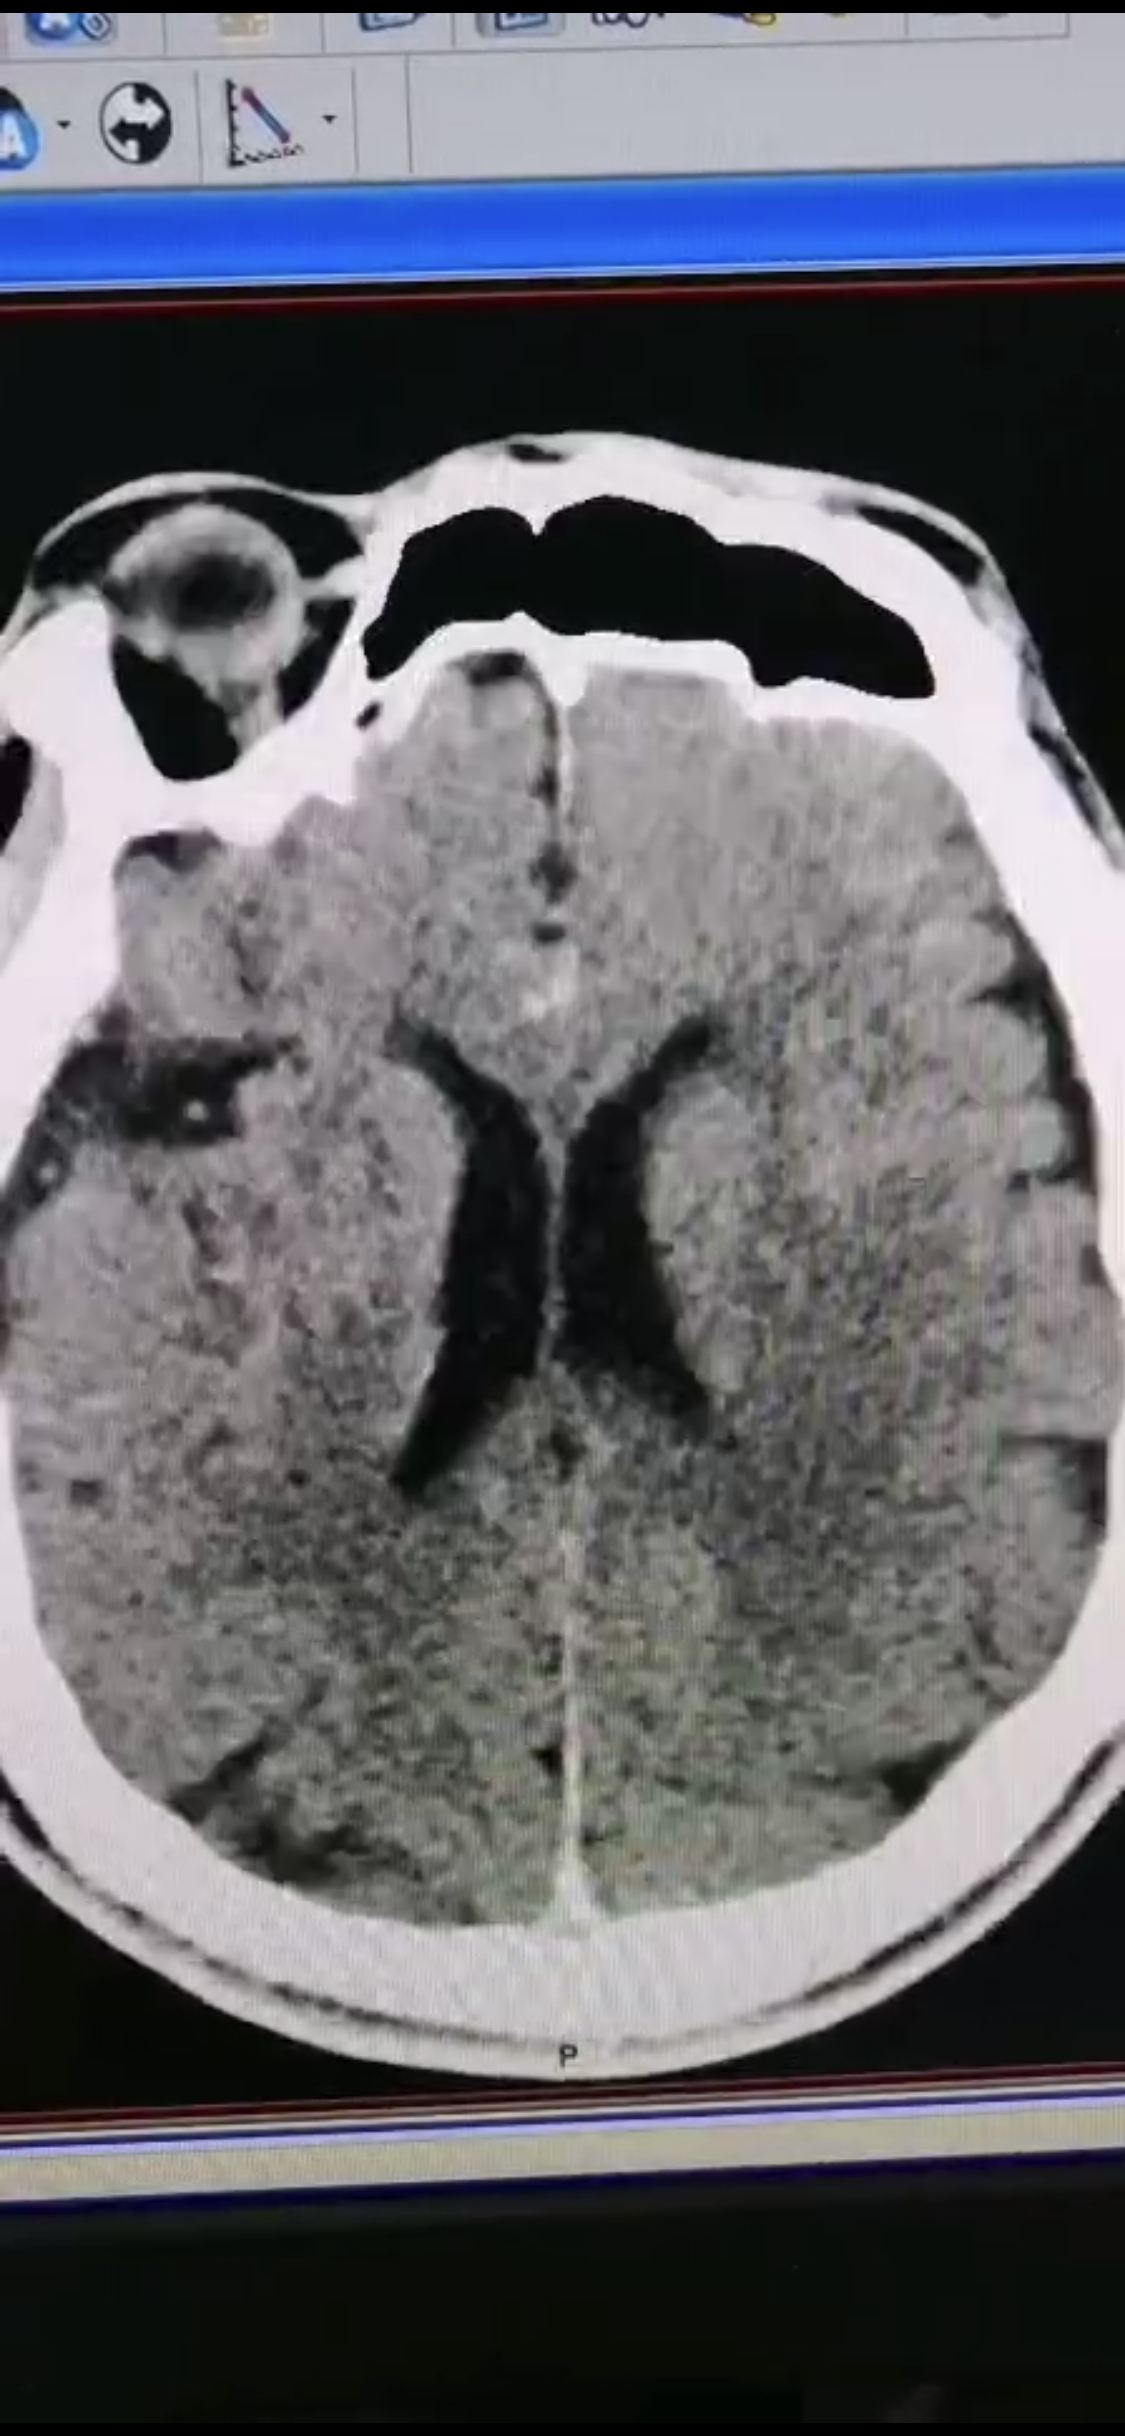

1周前房颤栓塞肱动脉,切开取栓后服用利伐沙班3天。突发偏瘫凝视3小时。上台看M3、A3血栓,国产普威森6f125cm抽吸导管高到位结合尼科3x20mm小支架,结合精细操作,m3和a3的血栓也可以轻松取出。不刺激血管。加造影射线16min两次取栓两个血管再通。

术后良好。